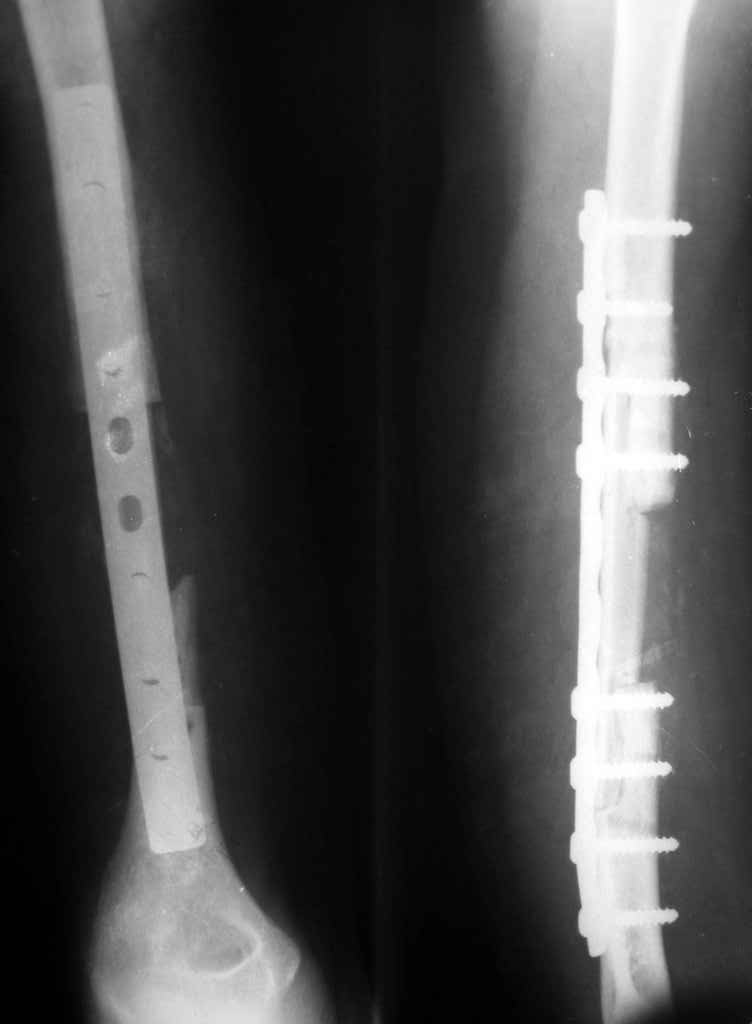

[Ortho] Ложный сустав плечевой кости

Владимир.Выделяем свои малоберцовую кость практически

полность.Выпиливаем замок там и тут. Синтез. Не типичный случай,но

перестраивается хорошо даже диафиз. рЕНТГЕН ПРИЛАГАЮ

Имя     : Рисунок1.jpg

Тип     : image/jpeg

Размер  : 14740 байтов

Url     : http://weborto.net:8080/pipermail/ortho/attachments/20100208/ce18b105/attachment-0003.jpg